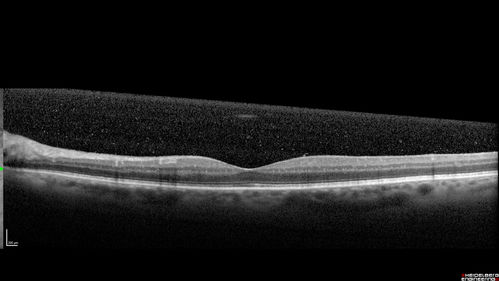

Chronic Endophthalmitis and Cystoid Macular Edema

VA 20/50 - Culture negative. Cleared with intravitreal antibiotics and decadron